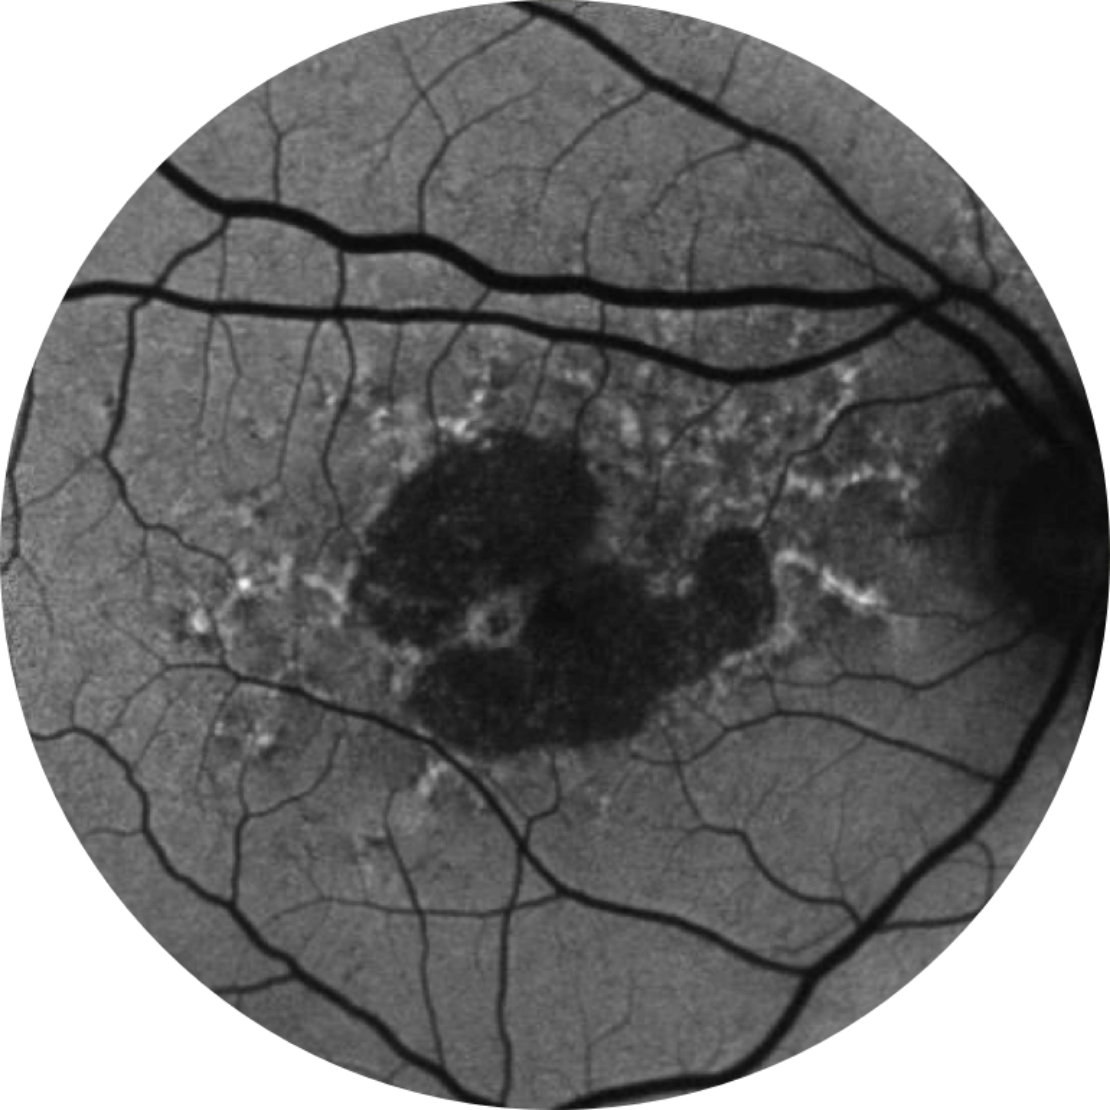

Photographie du fond d’un œil sain

Photographie du fond d’un œil atteint d’atrophie géographique

L’atrophie géographique se caractérise par une perte progressive et irréversible des photorécepteurs, de l’épithélium pigmentaire rétinien (EPR) et de la choriocapillaire sous-jacente.1,2

• région nettement délimitée dans la région maculaire avec une rétine atrophique, sans pigmentation

• vaisseaux sanguins choroïdiens sous-jacents visibles